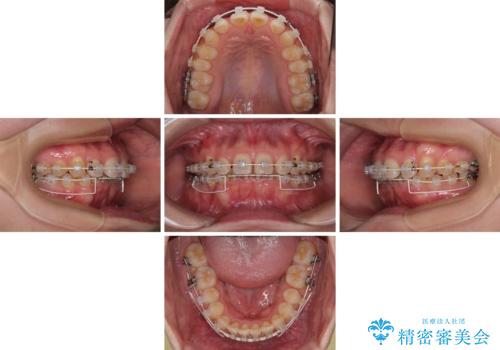

隠れた前歯が気になる ディープバイトのワイヤー矯正治療

- 下顎前歯が完全に隠れてしまっていることを気にして来院された患者様です。

下顎の臼歯が手前に傾斜していることで咬み合わせが深くなってしまい、下顎前歯が見えないほどに上顎前歯が覆い被さっている状態でした。

咬合力が強いことと、マウスピースを長時間装着する自信がないとのことで、ワイヤー装置にて矯正治療を行うこととしました。

下顎臼歯を起き上がらせるためにユーティリティーアーチを使用し、一気に深い咬み合わせを改善することができました。